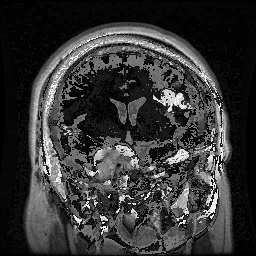

• Brain Tumor MRI Dataset (BMRI) [33]: The three datasets below are combined to create this dataset: figshare, SARTAJ, Br35H. There are 7023 MRI images of the human brain in this collection, divided into 4 categories: pituitary, glioma, meningioma, and no tumor. Images categorized as the ’no tumor’ class were obtained from the Br35H dataset.

The proposed QMedShield’s security is evaluated using a number of metrics and proved that it is resistant to various cryptographic attacks including brute-force attacks, statistical attacks, histogram attacks, and differential attacks. Throughout the section, 6 sample medical images BMRI1,BMRI2,CXR1,CXR2,LCT1,LCT2𝐵𝑀𝑅subscript𝐼1𝐵𝑀𝑅subscript𝐼2𝐶𝑋subscript𝑅1𝐶𝑋subscript𝑅2𝐿𝐶subscript𝑇1𝐿𝐶subscript𝑇2BMRI_{1},BMRI_{2},CXR_{1},CXR_{2},LCT_{1},LCT_{2} are taken (2 images from each dataset) to show the performance comparison. The selection of MRI, X-ray, and CT images for the encryption task aims to demonstrate the versatility and effectiveness of our model across various imaging modalities, showcasing its applicability and robustness in diverse clinical scenarios. Figure 11 shows the selected sample medical images and their corresponding encrypted images.

Refer to caption

(a) BMRI1𝐵𝑀𝑅subscript𝐼1BMRI_{1}

(b) CXR1𝐶𝑋subscript𝑅1CXR_{1}

(c) LCT1𝐿𝐶subscript𝑇1LCT_{1}

(d) BMRI2𝐵𝑀𝑅subscript𝐼2BMRI_{2}

(e) CXR2𝐶𝑋subscript𝑅2CXR_{2}

(f) LCT2𝐿𝐶subscript𝑇2LCT_{2}

(g) E(BMRI1)𝐸𝐵𝑀𝑅subscript𝐼1E(BMRI_{1})

(h) E(CXR1)𝐸𝐶𝑋subscript𝑅1E(CXR_{1})

(i) E(LCT1)𝐸𝐿𝐶subscript𝑇1E(LCT_{1})

(j) E(BMRI2)𝐸𝐵𝑀𝑅subscript𝐼2E(BMRI_{2})

(k) E(CXR2)𝐸𝐶𝑋subscript𝑅2E(CXR_{2})

(l) E(LCT2)𝐸𝐿𝐶subscript𝑇2E(LCT_{2})

Figure 11: Selected sample plain medical images and the corresponding encrypted cipher images